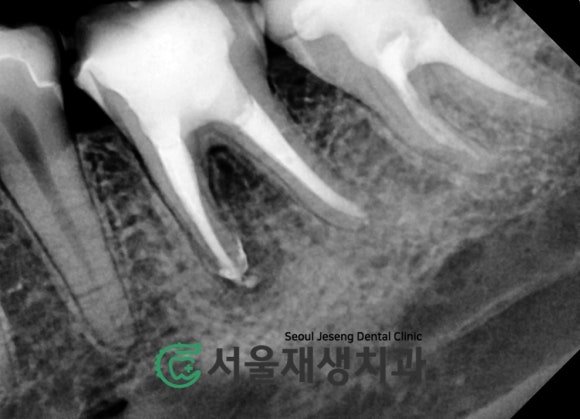

치료 전 후 사진

뿌리 끝까지

꼼꼼하게 치료되었습니다!

(재)신경치료의 마지막 단계,

튼튼한 크라운 씌워서 치아 보호하기